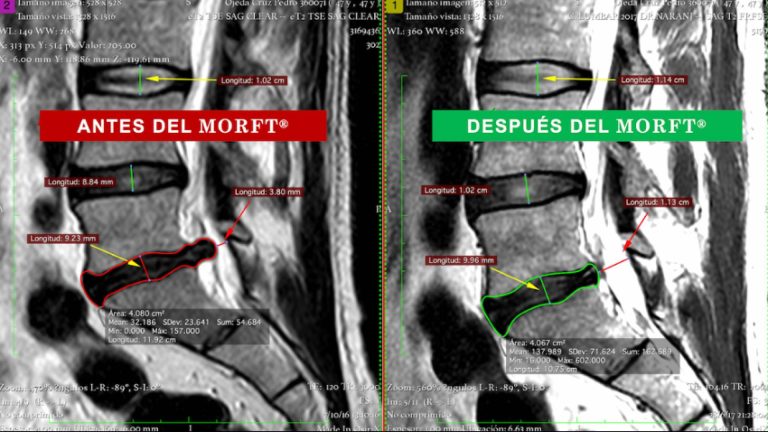

El método MORFT® rehabilita a pacientes que viven con protusión y/o hernia discal sin medicamentos ni cirugías

Para los que se preguntan cómo vivir con una protrusión o hernia discal, el doctor Carlos Oliveira, doctor en traumatología, especialista en medicina deportiva y creador del MORFT®, ofrece la recuperación total mediante este Método que consiste en ejercicios de rehabilitación de la columna vertebral y del aparato locomotor para sanar lesiones osteoarticulares y musculoesqueléticas de manera natural, inocua, no invasiva, no medicamentosa e indolora, sin riesgos ni contraindicaciones.

El Método Oliveira de Recuperación Funcional Total (MORFT®) es producto de los esfuerzos investigativos durante más de 38 años del Doctor brasileño afincado en España hace casi 30 años, que también es licenciado en Educación Física y Fisioterapeuta. Desde 1985, el especialista se ha dedicado a transformar vidas con esta propuesta para curar las enfermedades del sistema óseo y articular. El procedimiento ha sido aplicado con éxito en más de 14 países, como Estados Unidos, Francia, Italia, Alemania, Portugal, Egipto, India, México y Brasil, entre otros.

Más de 15.000 personas han sido tratadas con el método MORFT®, incluyendo atletas de élite, quienes han alcanzado su recuperación funcional. El sistema se aplica en tres fases. La primera es la de Descompresión articular o discal, basada en ejercicios de estiramiento activos y estáticos dirigidos a cada grupo muscular.

La segunda fase se denomina Potenciación y consiste en trabajar la fuerza y la resistencia de los músculos de acción biomecánica directa o indirectamente a la zona afectada. Mientras que estas dos primeras fases deben realizarse de manera presencial o semipresencial en los centros MORFT® Salud, la tercera etapa, la de Mantenimiento, es un plan de ejercicios que puede ejecutarse en la clínica o en casa, una vez que el paciente recibe el alta del tratamiento, para vivenciar un periodo de revisiones y ajustes de su programa de mantenimiento que evolucionará con el tiempo y los nuevos objetivos que decida el paciente reconquistar una vez que, recuperado totalmente, podrá llevar una vida libre de limitaciones.

Con resultados de recuperación funcional total en el 86 % de los casos, el método MORFT® sigue perfeccionándose para hacer que las personas den la bienvenida a una nueva vida, llena de salud, movilidad y vitalidad.